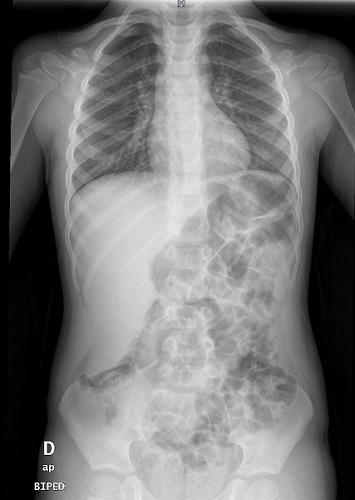

Se presenta el caso de un paciente varón de 4 años, sin antecedentes de interés, que consulta en el servicio de Urgencias por ingesta de cuerpo extraño. El paciente se encuentra asintomático y presenta una exploración física sin alteraciones. Para localizar el cuerpo extraño se realiza radiografía de tórax-abdomen, encontrándose como hallazgo incidental una hepatomegalia que llega hasta cresta iliaca derecha, no palpable en exploración física a su llegada. Tras rehistoriar dirigidamente al familiar del paciente y reexplorarle, se consulta al servicio de Radiología y se compueba que la imagen objetivada es del lóbulo hepático de Riedel (Fig. 1).

| Figura 1. Lóbulo de Riedel hepático como variante anatómica de la normalidad. Resto de estructuras abdominales sin alteraciones significativas. No alteraciones pleuroparenquimatosas significativas. Índice cardiotorácico en el rango de la normalidad |

El lóbulo de Riedel es una variante de la normalidad1-3. Se trata de una lengüeta de parénquima hepático dependiente del lóbulo derecho que puede llegar hasta la cresta iliaca, dando la falsa impresión de hepatomegalia.